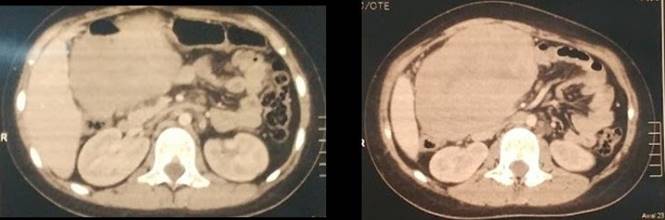

En mayo de 2019, consultó por dolor abdominal, vómitos de una semana de evolución y fiebre intermitente. Se realizó tomografía computada de abdomen donde se identificó a nivel mesentérico una masa inframesocólica derecha, lobulada, de contornos regulares que realzaba con contraste EV, de 141 x 99 x 133 mm (volumen tumoral: 965 cc). Resto del estudio sin particularidades (Figura 1).

Figura 1

Se repite PET-TC post quirúrgico no evidenciándose actividad metabólica (Figura 6).

Figura 6